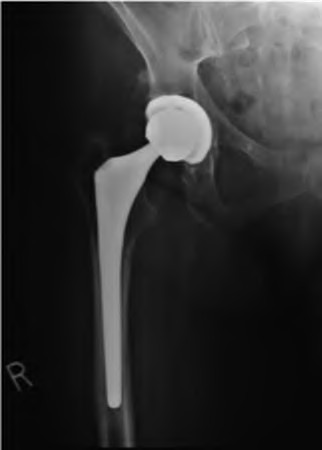

A 75-year-old man underwent total hip arthroplasty 10 years ago. He now reports mild groin pain which has been increasing lately. What is the most likely explanation for the finding in Figure A indicated with the arrows?

Osteolysis of the pelvis is a common complication associated with total hip arthroplasty. Osteolysis affects sockets with and without cement, and has been attributed to the biologic reaction to wear debris. With well-fixed cementless sockets, an expansile pattern of osteolysis is usually seen.

The radiographic appearance has a radiolucent area that starts at the implant-bone interface and expands into the cancellous bone away from the implant.

This pattern of osteolysis can be explained with the concept of effective joint space. This concept states that joint fluid and wear particles will flow according to pressure gradients and follow the path of least resistance.

The Level 5 review article by Chiang discusses osteolysis in further depth.